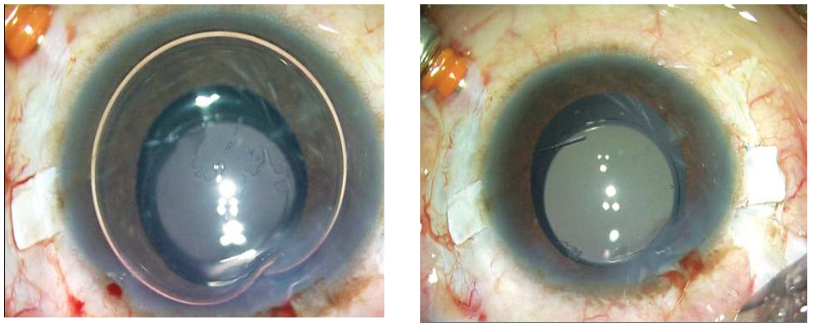

图3A和B:重组纤维蛋白胶在襻上巩膜瓣下注射,后封闭巩膜瓣。